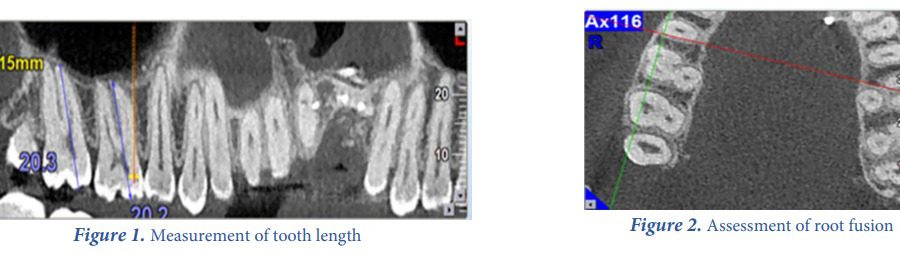

Root Canal Morphology of Maxillary Second Molars according to Age and Gender in a Selected Iranian Population: A Cone-Beam Computed Tomography Evaluation